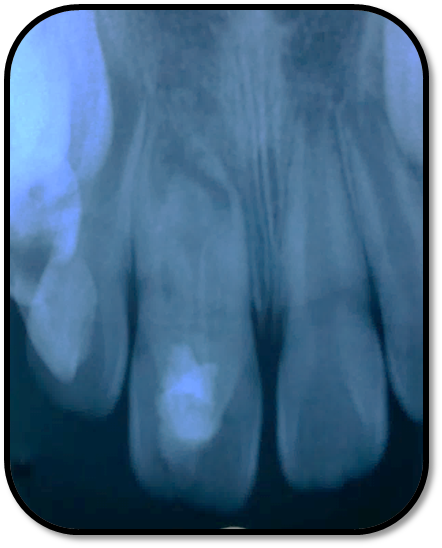

随访复查: 治疗完成后1个月复查:右上1临床检查无阳性体征,叩痛(—),冷测无反应,无松动,牙龈无红肿,充填物完好,牙冠略有变色, X线检查:牙根根继续发育,可见钙化影像形成,如图示 治疗完成后7个月复查:临床检查无阳性体征,充填物完好,牙冠变色局部发黑,叩痛(—),冷测无反应,无松动,牙龈无红肿,临床及 X线检查:牙根继续发育,如图示 治疗完成后17个月复查:临床检查无阳性体征,充填物完好,牙冠变色局部发黑,叩痛(—),冷测无反应,无松动,牙龈无红肿。X线:牙根继续发育,根尖孔已近闭合。如图 讨论: 1、牙内陷(Dens invaginatus):是牙冠在生物学矿化开始前的内陷引起的一种罕见牙齿畸形。文献报道,牙内陷的发生率为0.04-10%不等,好发于上颌侧切牙。尖牙,双尖牙,磨牙,下颌侧切牙也有报道。 2、Oehlers将牙内陷畸形牙分为Ⅰ型和Ⅱ型均为釉质阻射层包绕的细沟状透射影,不同的是Ⅰ型局限于牙冠部分,不超过釉牙骨质界。Ⅱ型超过釉牙骨质界延伸至根管内,但不与牙周膜相通。Ⅲ型表现为囊袋状或细沟状透射影,由釉质阻射层包绕,由牙冠部延伸至根尖区,与牙周膜相通。其中type Ⅱ和type Ⅲ型根管系统极其复杂。内陷部位的釉质和牙本质可能有缺陷或缺失,很可能与牙齿髓腔有交通,这些特点使得该部位易龋坏且易进展影响牙髓 ,而且此类牙牙周组织不连续,易形成深牙周袋 ;畸形舌尖随牙齿萌出妨碍咬合,造成咬合创伤,尖细的畸形舌尖髓角长入,易于磨损或折断,极易发生牙髓炎症或者根尖炎症。由于根管系统复杂,所以治疗极其困难。 3、牙内陷的治疗: a、内陷处易患龋—尽早窝沟封闭或PRR,已龋坏者及时治疗,避免发展为牙髓炎根尖炎。 b、畸形舌尖不妨碍咬合较圆钝者可不做处理 c、干扰咬合和高而尖的舌尖可磨除畸形舌尖选择间接盖髓术、直接盖髓、部分冠髓切断。 d、牙髓已受累根据牙髓感染情况和牙根发育情况选择根管治疗、牙髓再血管化、MTA根尖封闭、根尖诱导成形。 e、内陷程度较重的Oehlers Ⅲ型患牙,因内陷结构与根尖区牙周膜相通, 其内容纳的细菌物质导致根尖周炎发生时, 通过常规根管治疗并不能使病变痊愈,还需根尖切除术加MTA倒充填。 f、拔除患牙。 4、内陷盲袋清理治疗时应注意:a、推荐手用根管锉,不推荐旋转镍钛,因为内陷盲袋内壁覆盖釉质,而非牙本质壁,且盲袋形状不规则,使用旋转镍钛器械容易折断。b、推荐使用超声根管预备(Bishop,2008)。c、推荐2.5%-5.25%次氯酸钠化学预备。